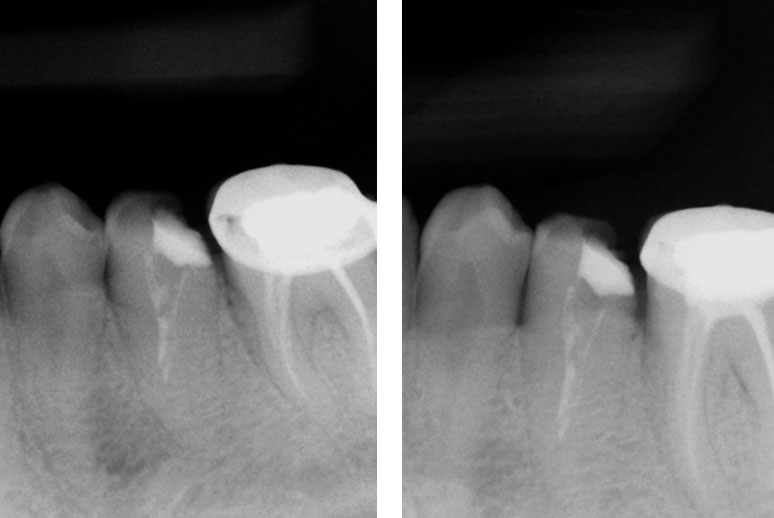

Pre-op

Pain in mandibular first molar after endo. Previous dentist unable to locate mesial canals. Obturated only the distal canal. Patient has generalized periodontal problems as well.

Pre-op, EDTA for 1 minute, After 1 minute EDTA

Red arrows show the two “white spots” indicating the calcified mesial canals.

Missed second distal canal (red arrow)

Pre-op & Post-op